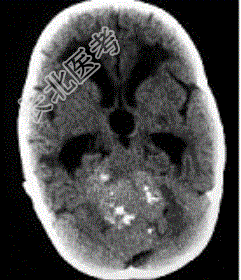

- 单项选择题成年男性患者,头痛、头晕、恶心, 病程2年余,结合影像图像选择最可能的诊断

A、星形细胞瘤

B、畸胎瘤

C、脑膜瘤

D、室管膜瘤

E、胶质瘤